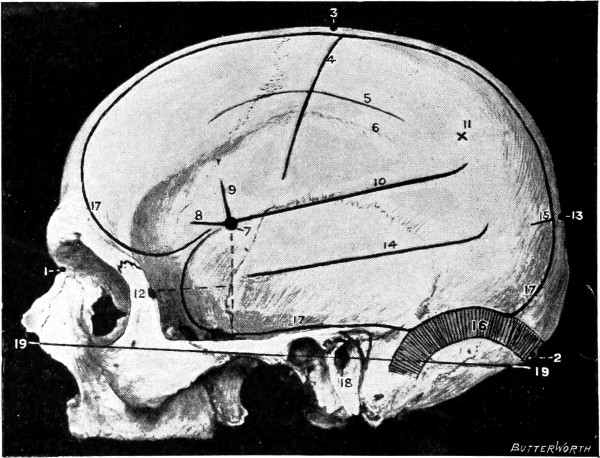

Fig. 1. Cranio-cerebral Topography. 1, The nasion; 2, The inion; 3, The mid-point between nasion and inion; 4, The Rolandic fissure; 5, The superior temporal crest; 6, The inferior temporal crest; 7, The Sylvian point; 8, The anterior horizontal limb of the Sylvian fissure; 9, The vertical limb of the Sylvian fissure; 10, The posterior horizontal limb of the Sylvian fissure; 11, The parietal prominence; 12, The malar tubercle; 13, The lambda; 14, The first temporo-sphenoidal sulcus; 15, The external parieto-occipital sulcus; 16, The lateral sinus; 17, 17, 17, The level of the base of the cerebrum; 18, The external auditory meatus; 19, 19, Reid’s base-line. (Reproduced, by the permission of Mr. H. K. Lewis, from the author’s work on ‘Landmarks and Surface-markings’.)

Firstly, the skull can be divided into two lateral halves by the surface-marking of the superior longitudinal venous sinus.

This sinus originates at the crista galli and, passing backwards along the attached margin of the falx cerebri, terminates at the internal occipital protuberance. It may be represented by a line drawn from the base of the nose (the nasion), over the vertex of the skull, to the external occipital protuberance (the inion)—this line corresponding in its course to the occasionally persistent metopic suture between the two halves of the frontal bone, to the sagittal suture between the parietal bones, and to the middle line of the upper or tabular portion of the occipital bone.

Secondly, each lateral half of the skull can be subdivided into supra- and infratentorial regions by a line which marks the external attachment of the tentorium cerebelli; in other words, by the line of the lateral sinus.

This sinus is represented by a line presenting a slight upward convexity, which is drawn from the external occipital protuberance to the upper and posterior part of the mastoid process of the temporal bone.

This artery is given off from the internal maxillary; after a short extra-cranial course it enters the skull through the foramen spinosum, and soon divides into two main terminal branches. The site of division corresponds to a point situated just above the centre of the zygoma.

The anterior branch passes at first in a forward and upward direction towards the anterior inferior angle of the parietal bone, and then turns upwards and backwards towards the vertex of the skull. The main ‘danger zone’ in the course of this vessel may be mapped out by taking points which lie respectively 1, 11⁄2, and 2 inches behind the external angular frontal process and an equal distance above the upper border of the zygoma. A line uniting these three points represents that part of the anterior division of the middle meningeal artery which is most liable to injury and which therefore most frequently requires exposure.

The uppermost point may, however, be regarded as the ‘site of election’ for exposure of the artery, as, in trephining over either of the two lower points, difficulty may be experienced in the removal of the disk of bone, since the posterior border of the great wing of the sphenoid tails off on to the anterior inferior angle of the parietal bone in such a manner that to effect a clean removal of the disk is often impossible. Another disadvantage to trephining low down lies in the fact that in about 30 to 40 per cent. of cases the artery occupies, in that situation, a canal in the bone.

The posterior branch passes almost horizontally backwards, parallel to the zygoma and supramastoid crest, towards the posterior inferior angle of the parietal bone. The vessel can readily be exposed[6] by trephining over the point at which a line drawn backwards from the upper border of the orbit, parallel to Reid’s base-line,[1] cuts another line directed vertically upwards from the posterior border of the mastoid process.

Both branches of the middle meningeal artery possess important relations to the cortex cerebri, the anterior branch passing upwards in relation to the precentral or motor area, traversing, from below upwards, the motor speech area (on the left side of the head), the centres for the movements of the face, upper extremity, trunk, and lower extremity. The posterior branch, on the other hand, passes backwards in relation to the temporo-sphenoidal lobe, one of the so-called ‘silent areas’ of the brain. Throughout their course the middle meningeal vessels lie between the dura mater and the bone.

The lower limit of the cerebrum can be mapped out in the following manner: From a point situated about 1⁄2 inch above the nasion a line is drawn outwards which follows the curve of the upper border of the orbit as far as the external angular frontal process, thence curving upwards and backwards to the Sylvian point (see below). The temporo-sphenoidal lobe sweeps forwards to the posterior border of the malar bone, and its lower limit lies practically flush with the upper margin of the zygoma. At and behind the ear the lower limit of the cerebrum corresponds to the suprameatal and supramastoid crests, subsequently following the curve of the lateral sinus from the mastoid process to the external occipital protuberance.

The Sylvian point represents the site of divergence of the three limbs of the Sylvian fissure. It lies 11⁄4 inches behind the malar tubercle and 11⁄2 inches above the upper border of the zygoma. The main posterior horizontal limb passes backwards and upwards to a second point situated 3⁄4 inch below the parietal prominence.

The vertical limb is directed upwards for about 1 inch, whilst the anterior horizontal limb passes forwards for about the same distance.

This, from a surgical point of view,[7] the most important fissure of the brain, is represented as follows: A point is taken in the median antero-posterior line which lies 1⁄2 inch behind the mid-point between nasion and inion, and from this point a line is drawn, for 31⁄2 to 4 inches, towards the mid-point of the zygoma. This line is inclined to the median antero-posterior line at an angle of 671⁄2° (three-quarters of a right angle).

In the representation of these two fissures, two points require to be determined—the malar tubercle and the lambda. Allusion has already been made to the former; the latter is usually readily located as the point of intersection of the sagittal and lambdoid sutures. A line uniting these two points corresponds in its middle third to the temporo-sphenoidal fissure, and in its posterior inch or so to the external parieto-occipital sulcus, a fissure separating the occipital and parietal lobes of the brain.